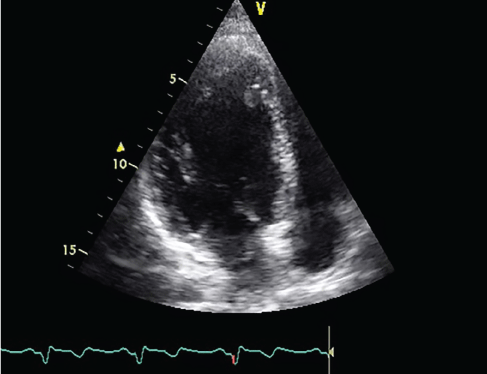

Pathologic examination of the mass was coherent with partially organized thrombus. At follow-ups after three months, echocardiographic examination showed recurrent apical mass (14 × 8 mm) (Figure 3). The patient was rehospitalized for adjusting anticoagulant therapy (INR was 1, 3) and with effective anticoagulant therapy the thrombus dissolved. The patient was discharged on warfarin and clopidogrel. Under strict control of INR the patient has been asymptomatic for about one year and thrombus haven't recurred.